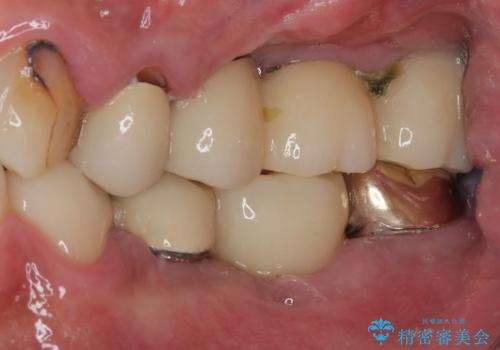

割れてしまった奥歯を1DAYインプラントで短期間治療

- 奥歯が割れてしまい、抜歯が必要となった患者様です。

以前にも歯が割れてインプラント治療を行いましたが、抜歯してからインプラント埋入→仮歯装着までに半年以上を要し、その間に残された歯への負担が大きくなり、セラミッククラウンが破折したことがありました。

そのため、当院に新しく導入した手法により、抜歯をした日にインプラントを埋入し、そのままを仮歯を装着することで、他の歯への負担を軽減する計画を立てました。